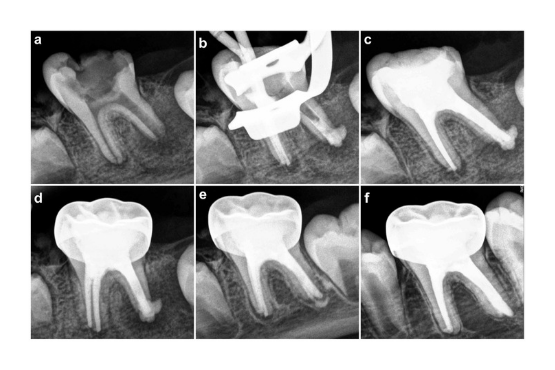

When your child’s cavity is deep and root formation cannot be induced, we artificially induce a barrier formation so that root canal therapy can be done for the tooth.